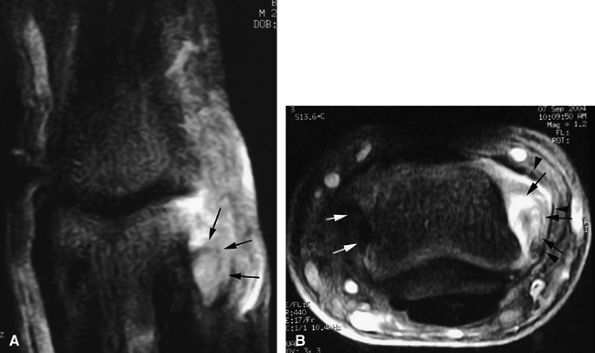

FIGURE 11.44 ● Acute rupture of the flexor digitorum profundus (FDP) tendon of the little finger in zone II. Coronal (A) and axial (B) post-contrast fat-suppressed T1-weighted images show retraction of a flexible proximal end (arrows) wrapping around the FDS tendon (asterisk).

FIGURE 11.50 ● Acute rupture of the flexor digitorum profundus (FDP) tendon in zone II. Sagittal post-contrast fat-suppressed T1-weighted image shows the gap, which measured 3 cm (arrows). Note the slight deficiency of the A2 pulley (arrowheads).